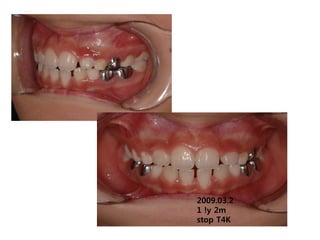

2009.03.2

1 !y 2m

stop T4K

2010.03.31

1yr later relapse